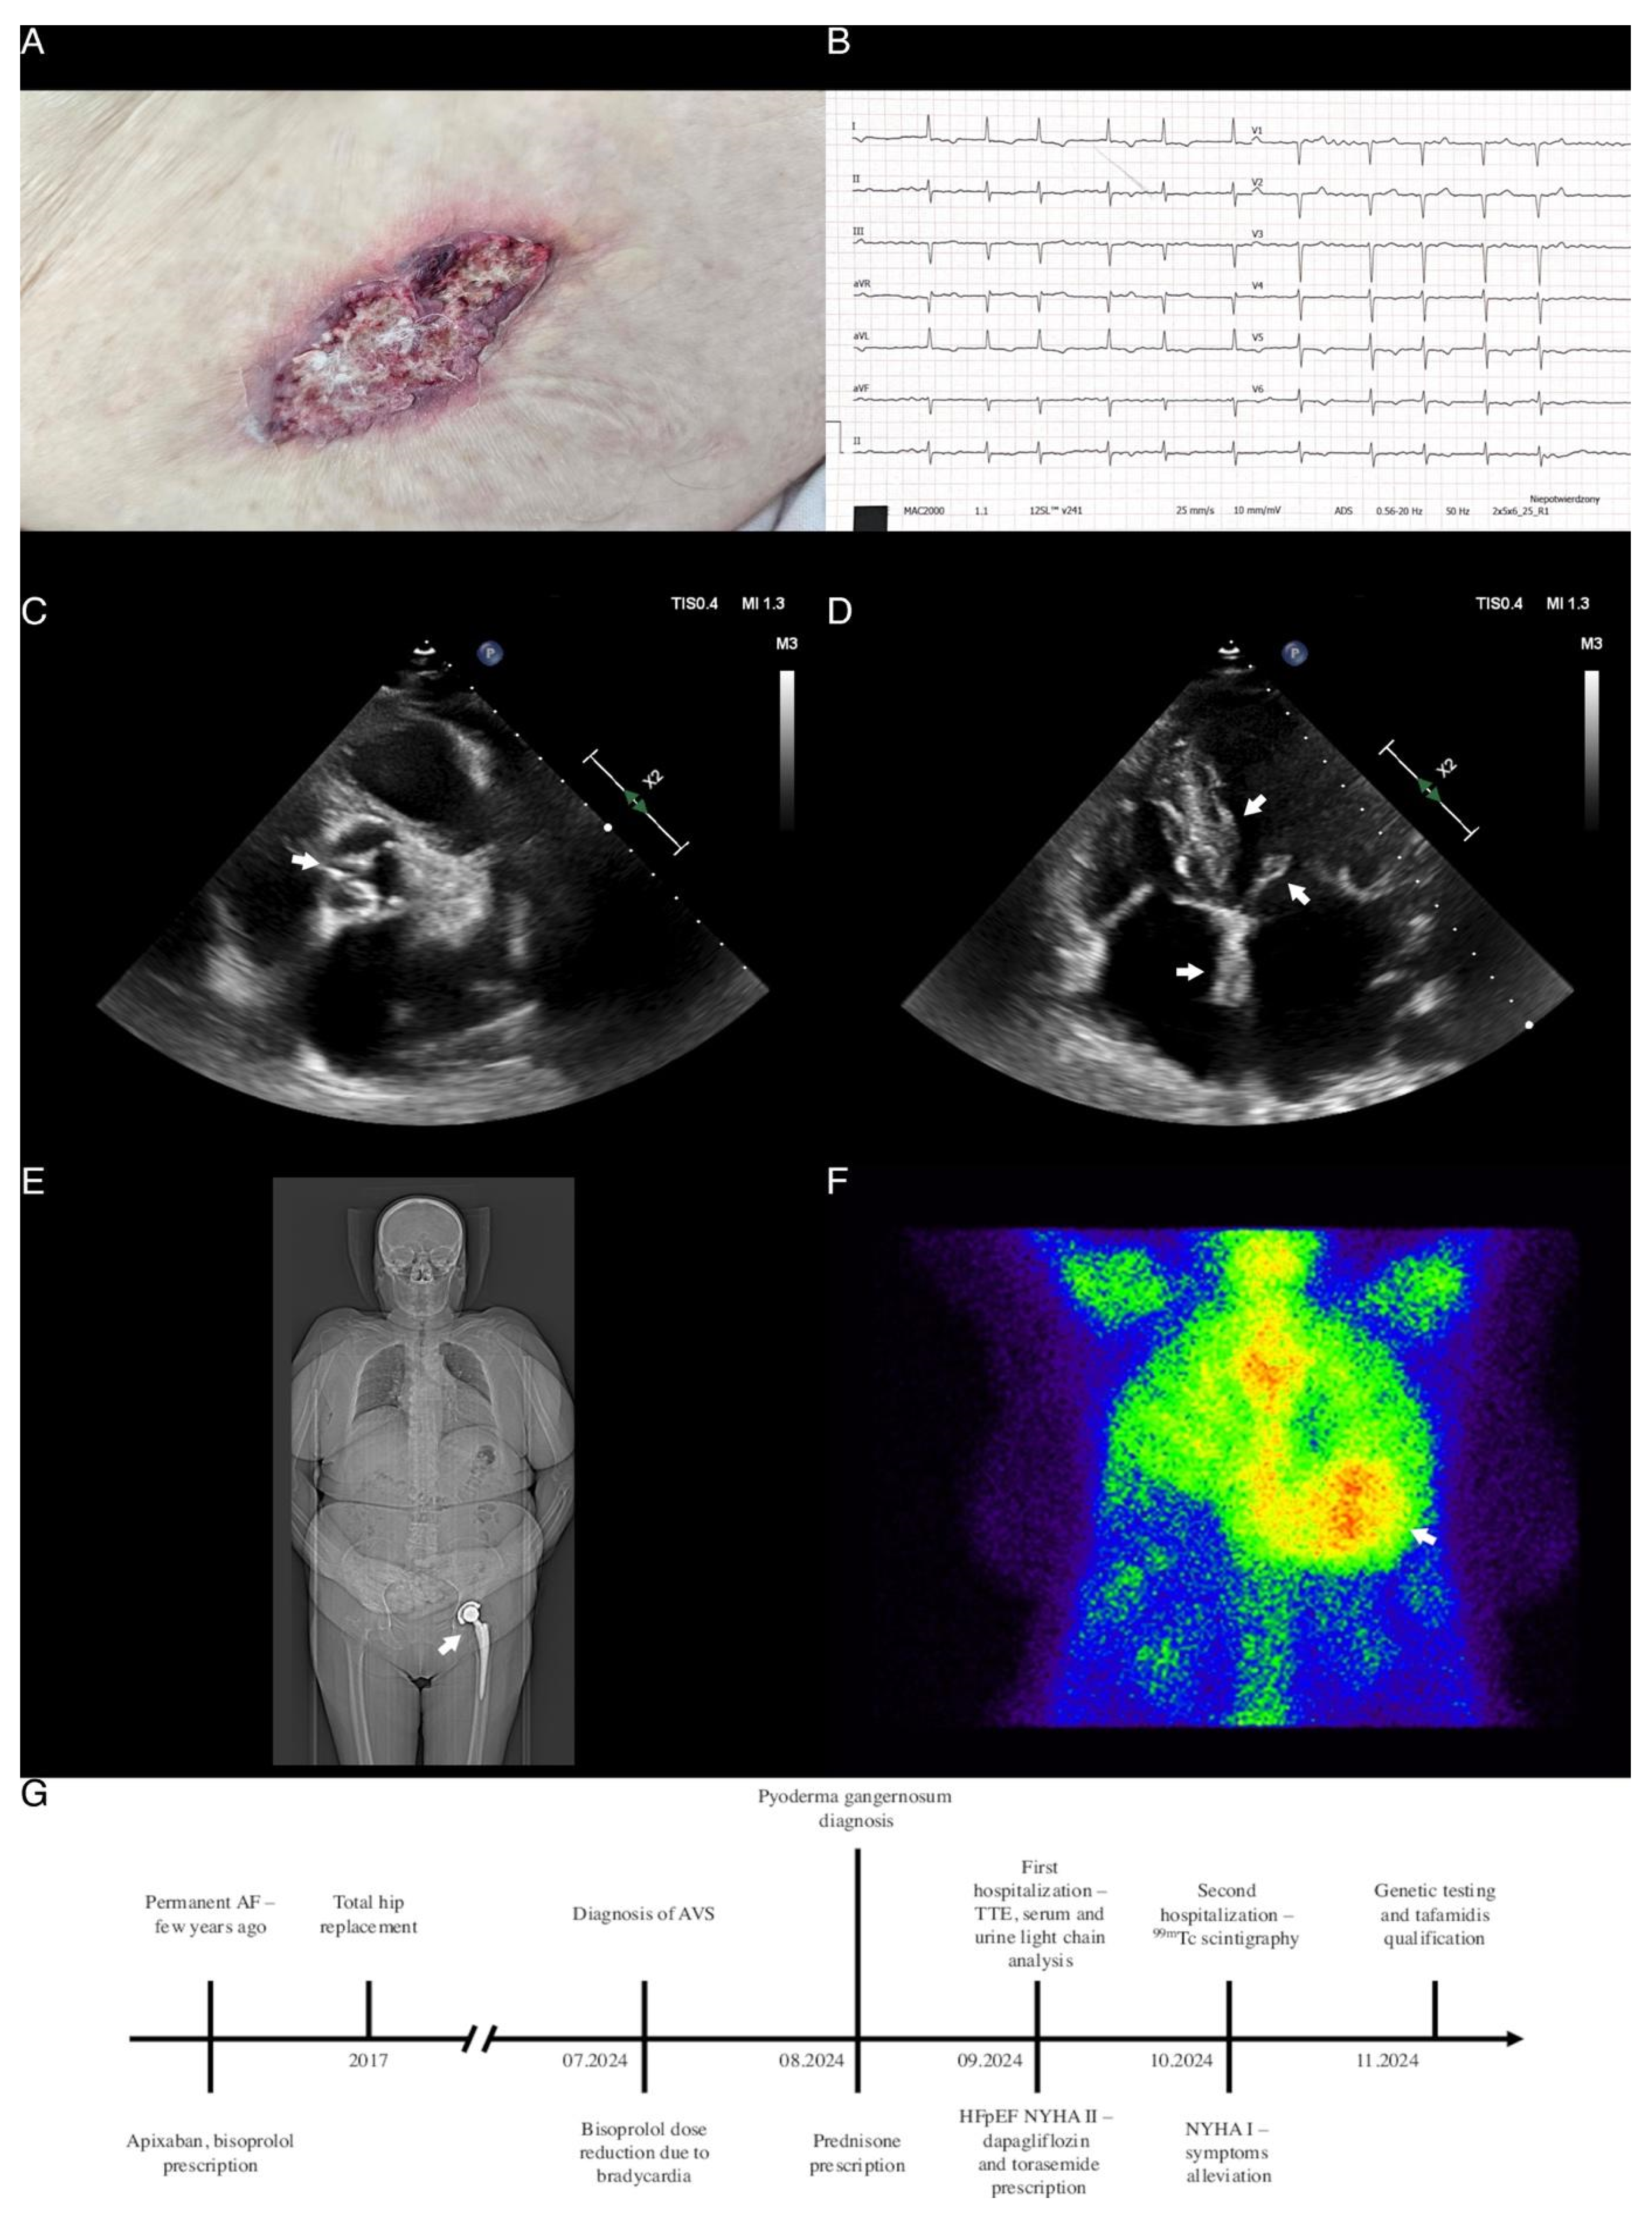

Multiple Red Flags of Cardiac Amyloidosis in a Single Patient: Clinical Manifestations of an Underdiagnosed Disease

Dąbrowski, E.J.; Kozłowska, W.U.; Lipska, P.O.; Matys, U.; Pogorzelski, S.; Kożuch, M.; Dobrzycki, S. Multiple Red Flags of Cardiac Amyloidosis in a Single Patient: Clinical Manifestations of an Underdiagnosed Disease. Diagnostics 2024, 14, 2812. https://doi.org/10.3390/diagnostics14242812